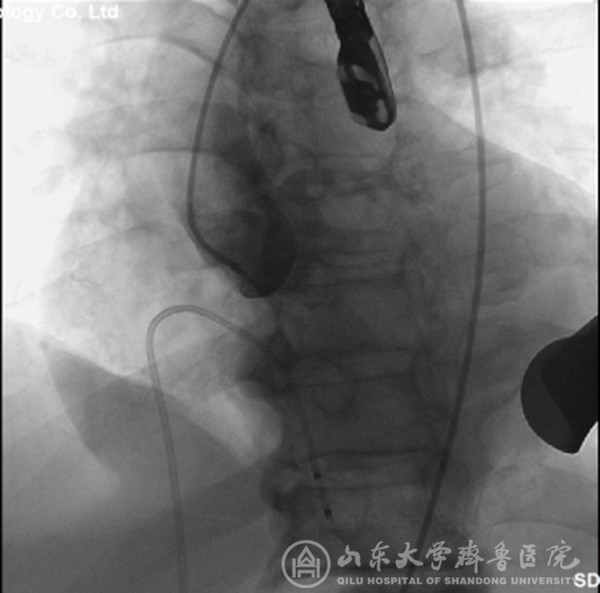

经过充分细致地准备,TAVI团队在复合手术室实施手术。根据患者的病情特点,术中做好各种应急预案,备好体外循环,维持血流动力学平稳。根据术前CT分析和术中主动脉根部造影情况(图1),选择最佳投照体位。选用29mm的介入主动脉瓣膜,经心尖途径,依次定位、顺序释放介入瓣膜(图2),造影及心脏超声检查示:人工瓣膜启闭功能正常,主动脉瓣无返流,未见明显瓣周分流(图3)。因患者心功能极差,手术操作过程中,多次出现频发及多源性室早、血压下降等情况,TAVI团队(心外科、心内科、麻醉科、手术室、心脏超声室等)医护人员齐心协力、整体配合,精心操作,积极对症处理,用时近2小时顺利完成手术。患者术后出现左心衰、血压低、尿量少等情况,给予积极处理,病情逐渐稳定。术后第2天拔气管插管,术后第5天转出监护病房。术后第7天,可下床活动,无心慌、胸闷等症状。术后第12天,病情稳定,治愈出院。术后2个月随访,患者基本日常活动不受影响,饮食正常,无心衰症状,恢复效果满意。

图3 置入介入瓣膜后,主动脉根部造影显示:主动脉瓣无返流